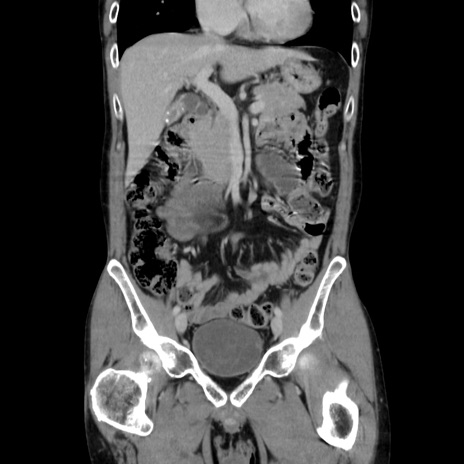

症例37(冠状断像)

【症例】40歳代 男性

【主訴】腹痛

【現病歴】4時間ほど前に電車に乗車中に臍部上より腹痛出現。徐々に増悪し起立困難となり、救急外来受診。生ものは数日食べていない。今朝お雑煮を食べた。

【身体所見】BT 36.8℃、BP 117/84mmHg、HR 91/min、SpO2 97%、苦悶様、腹部:臍上部広範囲圧痛あり、反跳痛±

【データ】WBC 8100、CRP 0.03